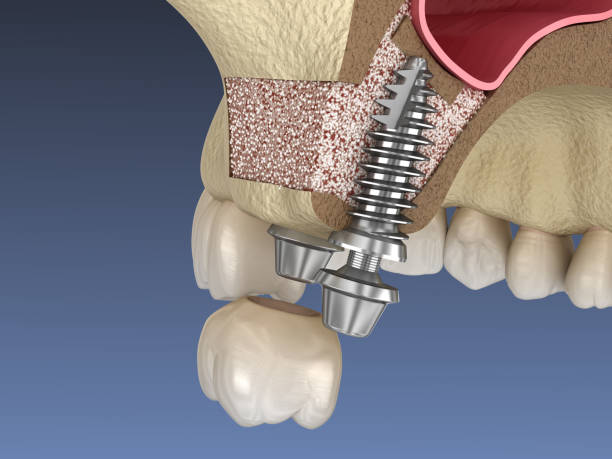

A sinus lift is performed when a person requires dental implants but does not have enough jawbone to hold the implants owing to bone loss. The operation improves bone volume by inserting bone into the gap between the molars and premolars. During the surgery, the sinus membrane is elevated to provide space for the bone.

There are various options for sinus lift surgery. The appropriate approach for you is determined by a number of criteria, including the type of bone transplant and the amount of bone in your jaw. Some of the basic steps are:

- Getting intravenous or oral sedatives to numb the region and make you as comfortable as possible during the process;

- Incisions at the rear of your gum tissue to expose the bone;

- Cut a tiny portion of the bone while taking the appropriate care to avoid cutting the sinus membranes;

- Lift the sliced part of the bone into the sinus cavity to elevate the membrane;

- Apply bone graft materials to the elevated region before putting sutures to seal the incisions in your gums.